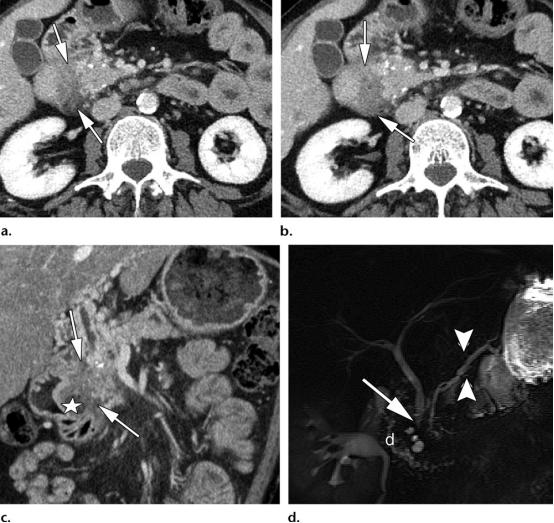

倾向于胰腺恶性肿物而非炎性病变的影像学表现。

(a图)冠状位CT图示胰腺导管与胰腺实质的比值大于0.5(用白色*表示的,弥漫扩张的主胰管的最大直径,与用白色长箭头表示的,表面覆盖的萎缩的胰腺实质,的比值);

(b图)轴位CT图示胰腺背景实质中弥漫性钙化,钙化被胰腺体部局灶性低密度病变(白色虚线圆圈包围的区域)推移至外周;

(c图)磁共振胆胰管成像示*管双**征,表现为扩张的胰管(两个平行排列的白色长箭头)以及扩张的胆总管(单一白色长箭头);

(d图)轴位CT图示泪滴征(黑色长箭头),肠系膜上静脉的泪滴样形态异常,这是由于血管被包裹,同时需要注意血管周围间隙内脂肪的丢失;

(e图)轴位CT图示肠系膜上动脉与肠系膜上静脉的比值≥1.0,或肠系膜上静脉的管径变窄(白色短箭头),与肠系膜上动脉(白色长箭头)的管径几乎相同。同时也需要注意血管周围间隙内脂肪的丢失。